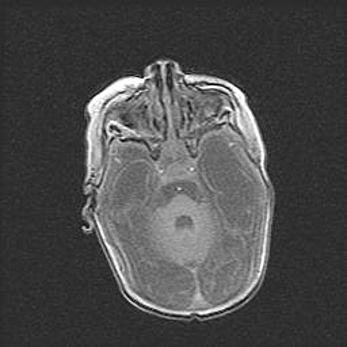

Церебральная ишемия II.

Возраст: 5 дней

Вес: 3400 г

Пол: женский

Окружность головы: 35 см

Срок гестации: 39 недель

Церебральная ишемия – это заболевание, характеризующееся недостаточностью (гипоксией) либо полным прекращением (аноксией) снабжения мозга кислородом по причине закупорки одного или нескольких сосудов. Это приводит к  что метаболическим расстройствам различной степени тяжести в тканях головного мозга, развитию коагуляционных некрозов и гибели нейронов.